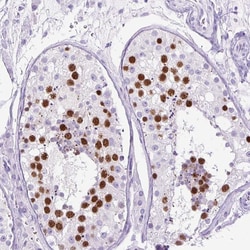

| AI227039; AI327394; AKT; Band25; CYK4; GAP; gtl11; GTPase; HsCYK-4; ID; ID-GAP; KIAA1478; Male germ cell RacGap; MGC99656; MgcRacGAP; mKIAA1478; PKB; PKB-ALPHA; PRKBA; protein CYK4 homolg; Protein CYK4 homolog; RAC; Rac GTPase activating protein 1; Rac GTPase-activating protein 1; RAC-ALPHA; Racgap1 | |

| Immunohistochemistry (Paraffin), Western Blot, Immunocytochemistry | |